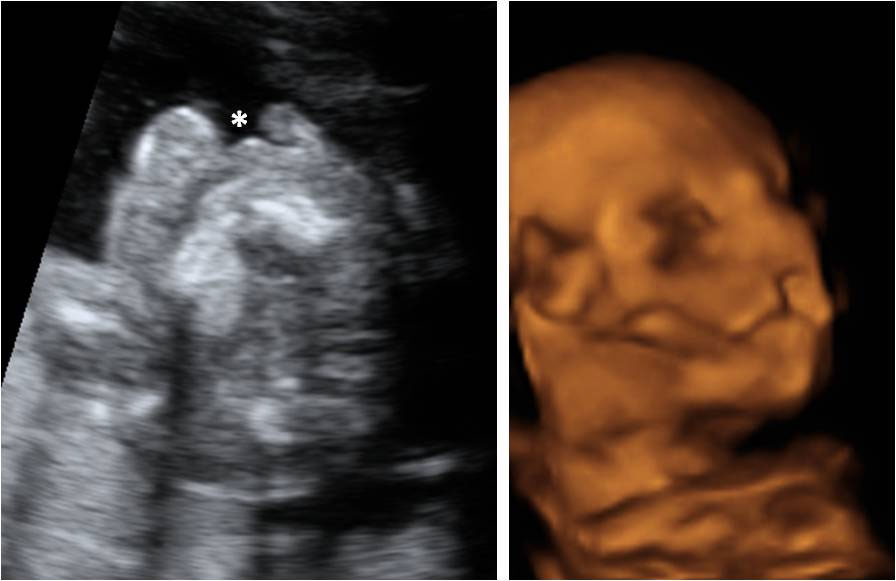

Ecografía Embarazo 4D Semana 20 - MALFORMACIONES FETALES

Cómo es un embarazo de trillizos

La ecografía en 3D de un embarazo de trillizos en la semana 20 puede resultar complicada de interpretar: piernas y brazos de los pequeños se confunden. Los fetos tienen poco espacio dentro del útero materno. Embarazo de trillizos Uno de los bebés está cabeza arriba y los dos hermanos se...